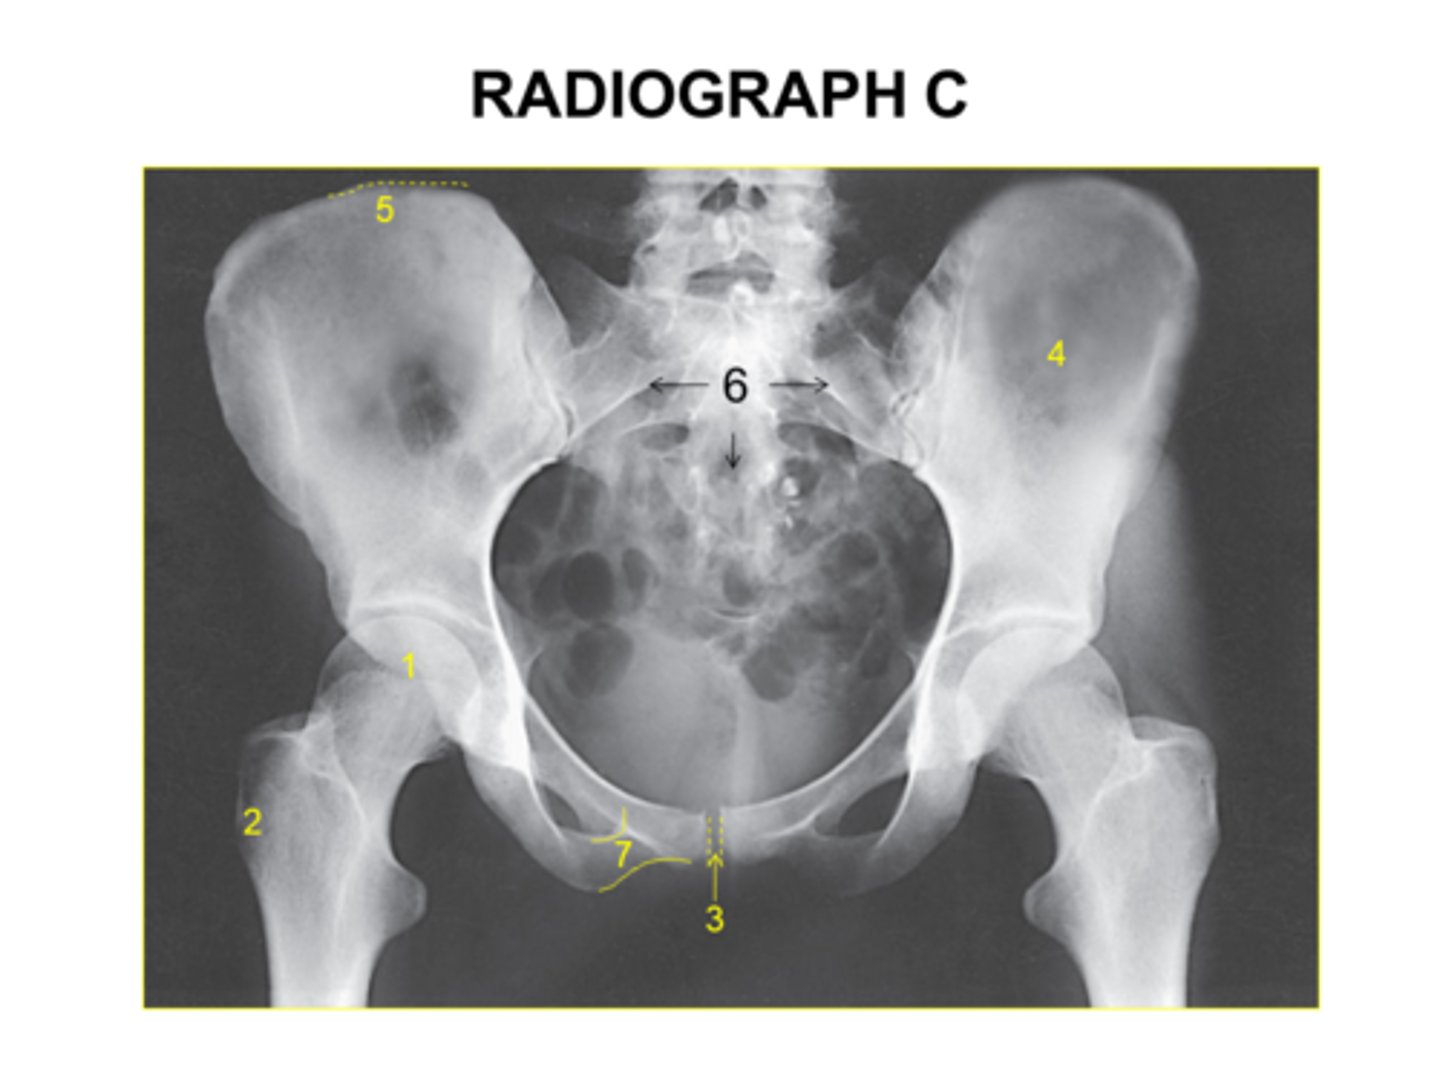

Identify the projection:

AP hip

AP oblique hip

AP pelvis

Lateral hip

The anatomy marked with #6 is the:

Acetabulum

Lesser trochanter

Obturator foramen

Greater trochanter

Ischial spine

Identify the anatomy marked with #7:

Pubic symphysis

Ischial tuberosity

Pubic bone

ilium

Is this pelvis rotated?

Yes

No

I'm not sure

The anatomy marked with #3 is the: